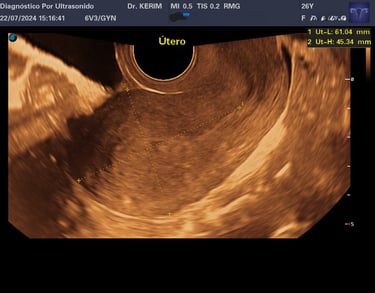

3.- Ultrasonido Pélvico Endovaginal

( o Abdominal)

La revisión ginecológica más precisa para tu útero y ovarios es por vía Endovaginal.

Al ser vía interna, obtenemos una imagen de alta resolución que un ultrasonido externo no puede dar. Fundamental para tu salud íntima.